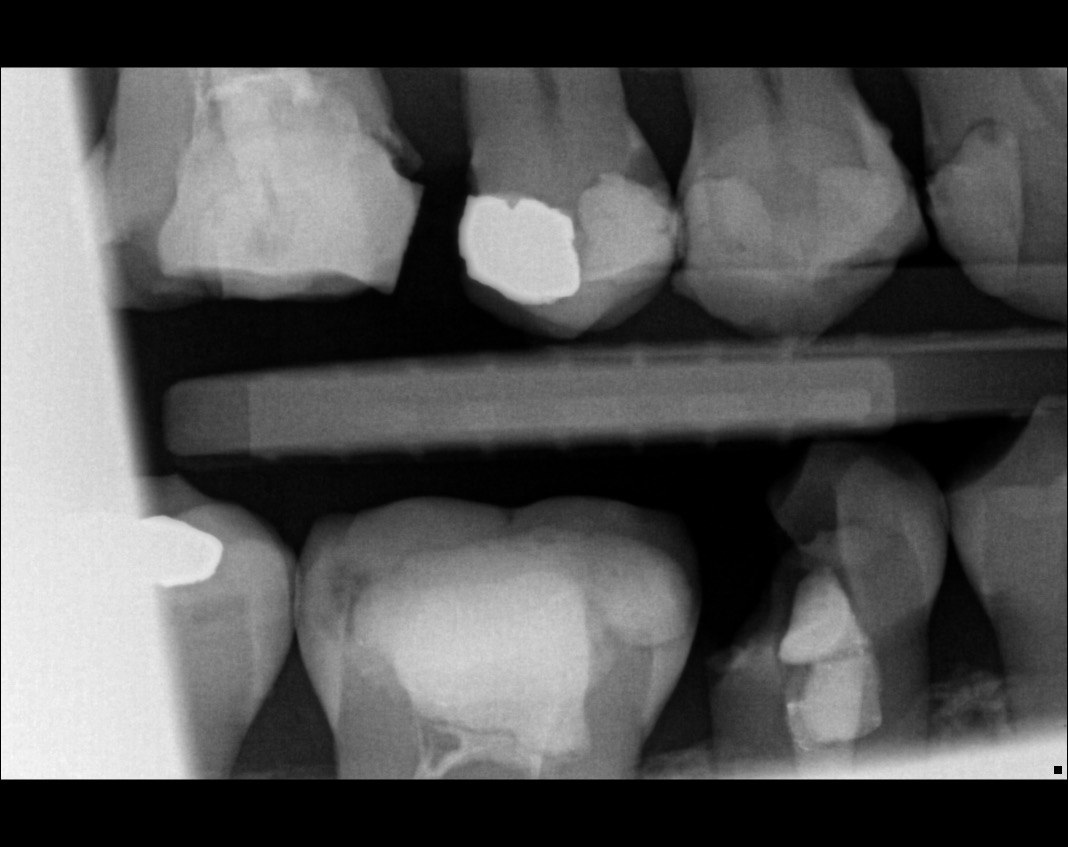

Question 1: What is the condition of the mesial surface of the tooth # 2.6?

Question 2. What is the condition of the mesial of the tooth # 2.7?

Question 3. What is the condition of the distal surface of the tooth # 2.7 and mesial surface of the tooth # 2.8 respectively?